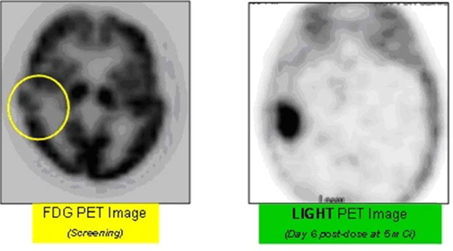

FDG Compared with LIGHT as a Cancer PET Imaging Agent in a Lung Cancer Patient with a Brain Metastasis

The images provided above are for illustrative purposes only and may not be indicative of all results.

The above illustrations do not refer to products approved by the FDA.

LIGHT is a small-molecule, broad-spectrum, cancer-targeted imaging agent that we believe has first-in-class potential for selective detection of tumors and metastases in a broad range of cancers. LIGHT is comprised of a proprietary phospholipid ether analog (PLE), acting as a cancer-targeted delivery and retention vehicle, covalently labeled with iodine-124, a short-lived PET imaging radioisotope. PET imaging used in conjunction with CT scanning has now become the imaging method of choice in oncology. In studies to date, LIGHT selectively illuminated malignant tumors in 52 of 54 animal models of cancer, demonstrating broad-spectrum, cancer-selective uptake and retention. Investigator-sponsored Phase 1-2 trials of LIGHT as a PET imaging agent are ongoing across 11 solid tumor indications. Initial positive imaging results have been established in patients with lung and brain cancers. These human trials, if successful, would likely provide proof-of-concept for LIGHT as a PET imaging agent with the potential to supplant the current “gold standard” agent, 18F-fluoro-deoxyglucose (FDG), due to what we believe to be LIGHT’s superior cancer-specificity and more favorable logistics of clinical use. As a chemically identical biomarker for HOT, we believe that LIGHT tumor uptake data could accelerate clinical development of HOT by guiding selection of indications for HOT Phase 2 trials and potentially be used in such trials to identify suitable patients and assess therapeutic efficacy. For the same reason, and in view of the quantitative nature of PET imaging, LIGHT imaging may be capable of estimating an efficacious dose of HOT in individual patients.